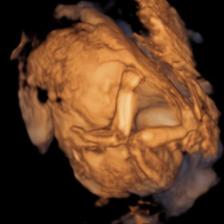

Novinky a tretie bábo